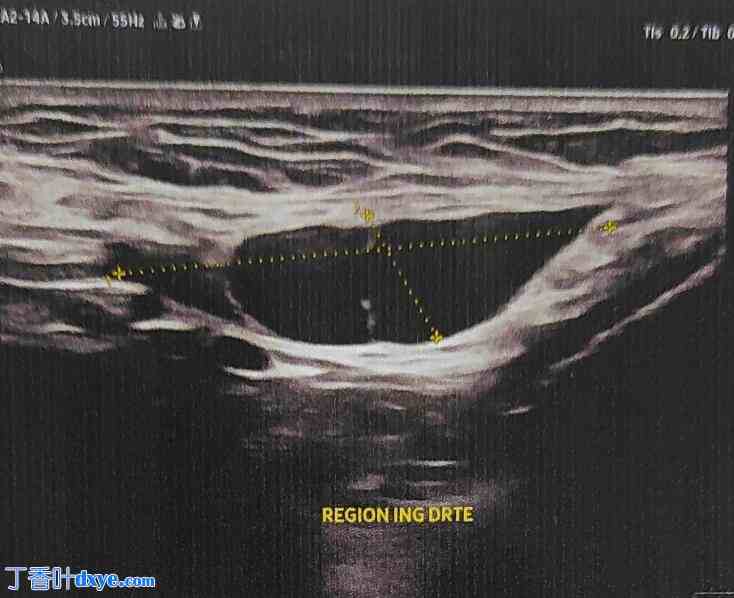

尽管多次会诊,仍未确诊,医生建议保守治疗。然而,由于疼痛加剧且肿胀持续存在,患者寻求进一步检查。临床检查发现右侧腹股沟区有一4厘米大小的肿块,质地较硬,无压痛,活动度良好,与表面皮肤无粘连,无炎症表现。超声检查显示腹股沟管至大阴唇方向有一边界清晰的囊性病变,直径40 mm(图1)。这些发现提示努克氏囊肿,患者被安排行择期切除术。

图1

超声检查显示一个大小为4.1 × 2.3 cm的囊性结构,内部有致密肿块。